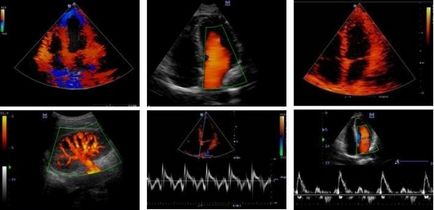

Imagini în modul Doppler color: se poate observa fluxul sanguin

Undele sonore sunt reflectate de obiecte în mișcare, echipament procesează semnalele recepționate și creează o imagine bidimensională multicoloră. Era doctorul o vede dacă există ceva greșit în modul în care sângele curge prin vasele. În ceea ce privește aplicațiile acestei tehnici, acestea sunt puține:

Este o metodă de scanare duplex include RDC sau Doppler color. Deci, ce este, cu ultrasunete RDC? Este tot aceeași ecografie, dar rata de diferite fluxul de sânge, marchează cu culori diferite. Ca urmare, imaginea rezultată toate vasele mari obține culoarea lor, poate fi văzut și starea rezervelor de sânge. Este acest proces necesită o senzori cu ultrasunete special configurate, și, de asemenea, permite să observe primele stadii de dezvoltare a tumorii.